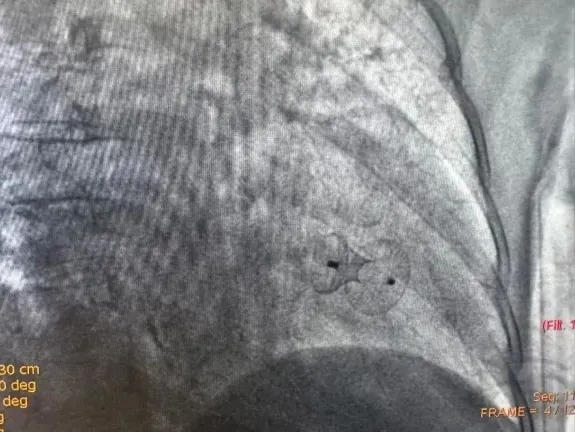

冠脉介入术后1周,在丁春华主任带领下,为患者实施经皮室间隔缺损封堵术。术中,团队凭借丰富经验与精准操作,在DSA(数字减影血管造影)引导下,封堵器被精准送达穿孔部位,并实现成功释放。经心脏超声检查阻断了心室间的异常分流,达到手术终点,患者自诉呼吸顺畅,胸闷症状立即缓解,整个手术过程历时1小时,全程生命体征平稳。

DSA下室间隔缺损封堵术后